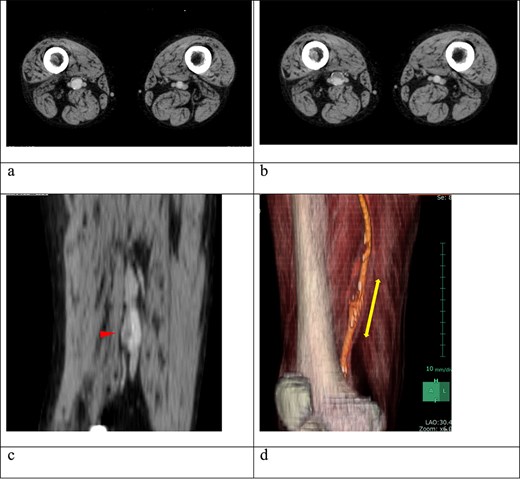

A 62-year-old male patient presented with an asymptomatic 15-mm-diameter right SFA aneurysm on computed tomography (CT). The patient had a history of chronic limb ischemia of the left upper extremity due to proteinase 3-specific antineutrophil cytoplasmic antibody (PR3-ANCA)-associated vasculitis. He also had a history of deep vein thrombosis (DVT) and pulmonary embolism secondary to antiphospholipid syndrome (APS) and systemic lupus erythematous, requiring pulmonary thromboembolectomy, right deep vein thrombectomy, and inferior vena cava filter placement. Although the 12-mm-diameter SFA aneurysm was detected at the time of DVT evaluation, no further imaging follow-up was performed after DVT treatment. Given the aforementioned medical history, the patient was on anticoagulation therapy with 10 mg/day of rivaroxaban and immunosuppressive therapy with 6 mg/day of methylprednisolone and 100 mg/day of azathioprine. A contrast-enhanced CT revealed the right SFA aneurysm, measuring 15 mm in diameter. The aneurysm was located ~6 cm proximal to the knee joint. A comparison with the CT scan for DVT recurrence evaluation obtained 2 years prior revealed an increase in the intraluminal thrombus within the aneurysm (Fig. 1). CT angiography of the distal lower extremity revealed no evidence of occlusion and recurrent DVT.

(a) Contrast-enhanced computed tomography (CT) performed 2 years earlier showed no thrombus in the right superficial femoral artery (SFA) aneurysm. (b) Despite ongoing oral anticoagulation therapy, preoperative contrast-enhanced CT revealed thrombus progression within the aneurysm, which was located 6 cm proximal to the knee and measured 15 mm in diameter. (c) The sagittal section of the contrast-enhanced CT showed an irregular thrombus on the inner wall of the aneurysm (arrow). (d) A three-dimensional-reconstructed contrast-enhanced CT identified the SFA aneurysm (arrow).

Despite the implementation of anticoagulation therapy, the intraluminal thrombus within the aneurysm continued to grow. Consequently, surgical resection was deemed necessary to prevent potential embolization.